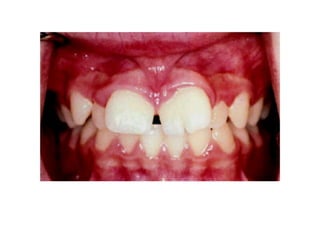

1. Supernumerary Teeth

Merupakan gigi yang jumlahnya melebihi

jumlah normal.

• Mesiodens

• Peridens

• Distodens